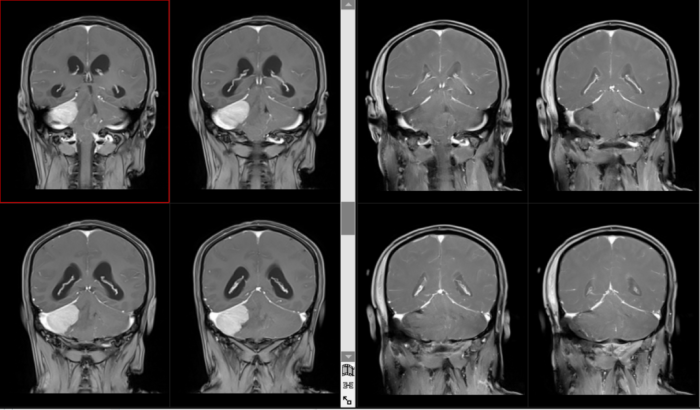

近期,我院神经外科团队成功为一名40岁男性患者实施巨大小脑幕下脑膜瘤近全切除术。该患者肿瘤体积接近5cm,压迫脑干,挤压第四脑室并引发梗阻性脑积水,病情极度凶险。该科团队凭借精湛的显微技术与丰富经验,成功为患者拆除颅内“定时炸弹”,患者术后顺利康复。

患者因反复头痛8月余来到我院神经外科就诊。据患者自述,半年前已在外院检查发现小脑幕下脑膜瘤,但因肿瘤巨大、位置险要、紧邻生命中枢,外院评估手术风险极高,无把握完成手术。

入院后,我院进一步完善影像学检查,初步诊断为右侧小脑幕下脑膜瘤,肿瘤最大径接近5cm,属于巨大脑膜瘤。肿瘤压迫脑干,挤压第四脑室,造成梗阻性脑积水,颅内压力持续升高,患者随时可能发生头痛加剧、意识昏迷、呼吸心跳骤停,病情极其危急。

在科室负责人李深誉主任医师主持下,全面评估手术风险、制定周密的显微手术方案与应急预案,充分做好术前准备。手术中,团队在高清显微镜下精细操作,仔细分离肿瘤与小脑、重要血管及神经结构,分块切除肿瘤组织,最终实现肿瘤近全切除,完美保护了所有神经功能结构,手术取得圆满成功。